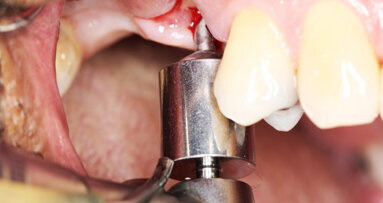

Dvaadvacetiletý pacient byl na naši kliniku odeslán z důvodu bolestivosti zubů 45 a 46. Jednalo se o celkově zdravého pacienta s mírnou až akutní bolestivostí zubů na poklep. Odesílající lékař byl znepokojen celkovou anatomií. Po zhotovení preoperativního rentgenového snímku (Obr. 4) byl proveden trepanační otvor pomocí vrtáčku Crown Cutter a vrtáčku s neaktivní pracovní částí (KOMET/Gebr. Brasseler). Úprava obrysu kavity byla provedena Start-X-ultrazvukovou koncovkou č. 1 a Muellerovým vrtáčkem č. 3 (Mani, Inc.; obr. 5).

Vstupy do kořenových kanálků byly zkalcifikované, přístup byl získán pomocí nástroje ProTaper SX, který byl veden kartáčovitým pohybem. Opracování kanálků bylo provedeno 10.02 K-Flexofilem (DENTSPLY Maillefer) za pomocí Glyde Gel (DENTSPLY Maillefer). Průchodnost byla ověřena PathFily a kanálky byly opracovány za použití ProTaper Systému (DENTSPLY Maillerfer). Po apikálním tvarování byly čtyři kanálky opracovány nástrojem ProTaper F3 s irigací 5% roztokem hypochlornanu sodného. Finální výplach byl proveden ultrazvukově aktivovaným 5% roztokem hypochloridu sodného, 40% roztokem kyseliny citronové a 95% etanolem. Kořenová výplň byla zhotovena pomocí Alpha II a Beta zařízení za použití techniky kontinuální kondenzační vlny a vstup do kořenových kanálků byl uzavřen kompozitem (Gradia Flow; Obr. 6).